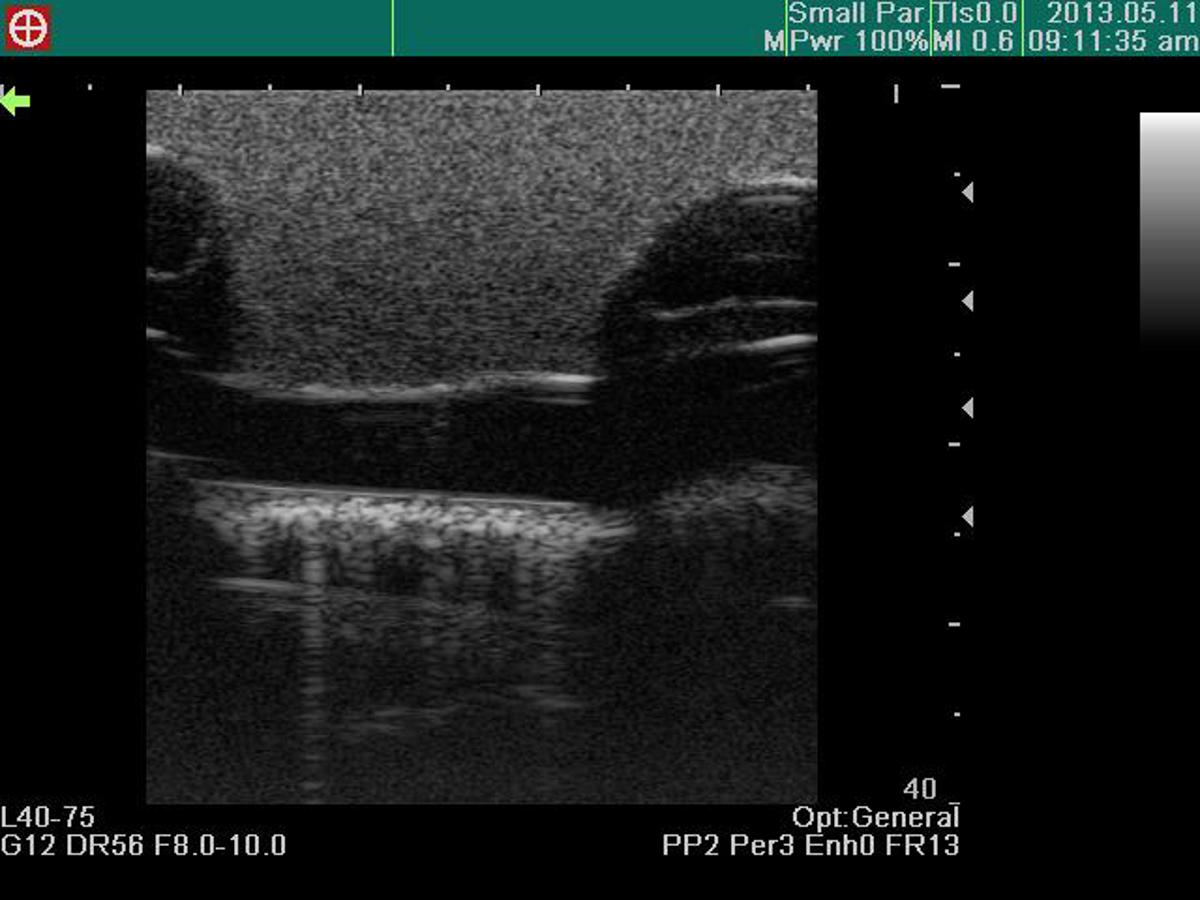

Excellent ultrasound image

Confirmation of ventricles, ribs, pericardium, liver and main artery under ultrasound scanning

Recognition of anatomical landmarks using ultrasound

Assessment of level and volume of pleural effusion